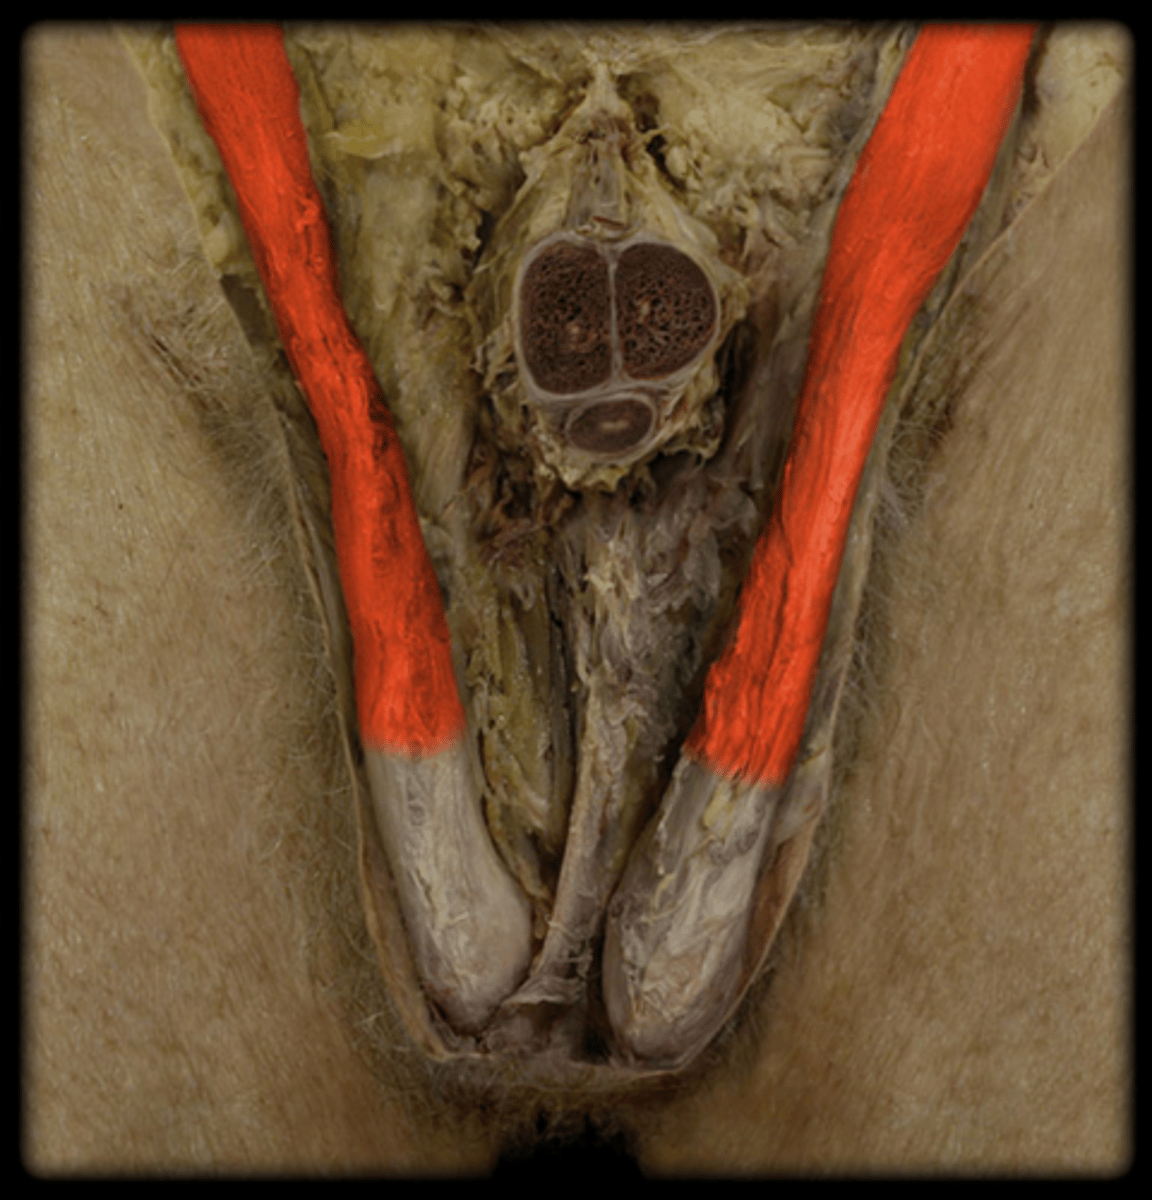

Testis

Epididymis

Spermatic Cord

Vas Deferens

Corpus Cavernosum